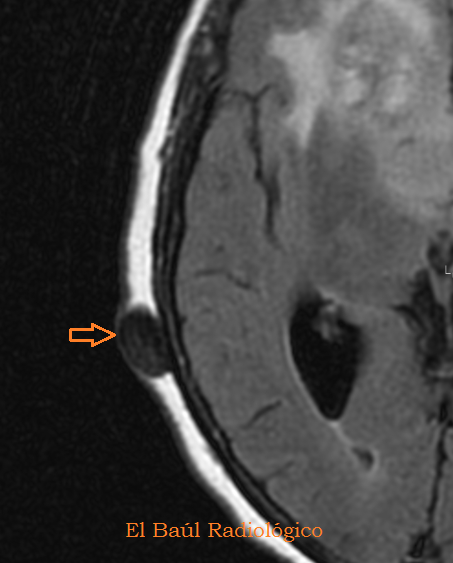

FIGURA 6) Los quistes sebáceos tambien se detectan en las exploraciones de TRM. Se presentan como un nódulo hipodenso, bien delimitado, que no tiene relación con el cráneo.

(Sebaceous cystsare detectedalsoin the explorations ofMRI.They appear ashypodense, well-defined nodes, which has no relation to the skull).

FIGURA 7) Por su elevada concentración en sales cálcicas, los quistes sebáceos no varían en las imágenes potenciadas en T2 (FLAIR-T2).

(Due toits high concentration ofcalcium salts theydo not changeinT2-weightedimages(FLAIR-T2).